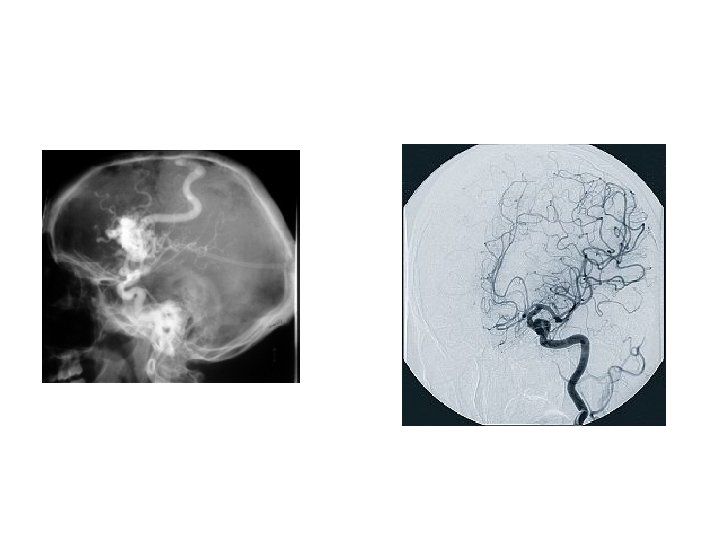

ANGIOGRAPHY/ CARDIOVASCULAR INTERVENTIONAL TECHNOLOGY is a specialized radiographic examination where the images of the blood vessels of the body are demonstrated by injection of contrast media. 61

ANGIOGRAPHY is a specialized radiographic examination where the images of the blood vessels of the body are demonstrated by injection of contrast media 64

66

Angiography 68